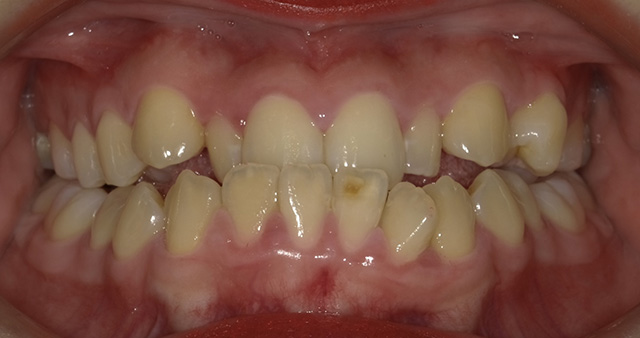

上顎(じょうがく)の糸切り歯(犬歯)が歯並びから飛び出している状態を八重歯(やえば)といい、歯並びが凸凹(でこぼこ)になっている状態を、乱ぐい歯といいます。これらは歯並びが悪い状態を指し、叢生(そうせい)とも呼ばれています。顎(あご)が小さいと歯が生える十分なスペースがないため、歯と歯が重なり合って、叢生が生じると考えられています。叢生は、歯みがきの時に歯ブラシが届きにくく、歯と歯の間に食べかすがたまり、むし歯や歯周病が起こりやすくなります。